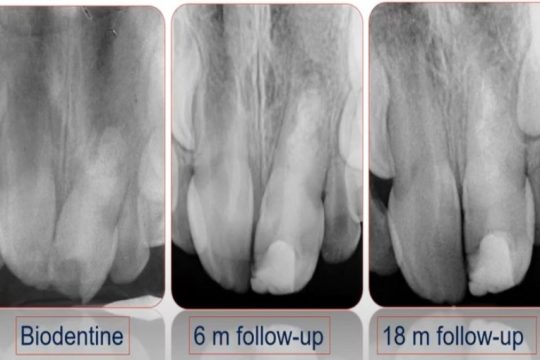

Presented by the Department of Pediatric Dentistry (Ghent University), in the context of 10 years’ experience with Biode...